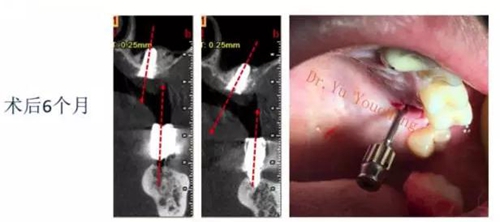

系列課開播前小編為大家預(yù)告了一例上頜竇外提升術(shù)后種植體方向改變的病例,當(dāng)時(shí)頓生種種疑惑:“真的么?怎么會(huì)?怎么辦!!”在本次課程中余教授給出了答案:上頜竇外提升同期種植有一重要的因素,即種植體初期穩(wěn)定性的獲得。該患者由于其骨量的嚴(yán)重不足,雖然可通過大直徑覆蓋螺絲保證種植體不至于滑落,但隨著竇粘膜的運(yùn)動(dòng)和部分移植骨的吸收,種植體方向最終受到了影響,這也提示我們在制定治療計(jì)劃過程中應(yīng)慎重考慮這一因素,以確保更好的種植預(yù)后效果。